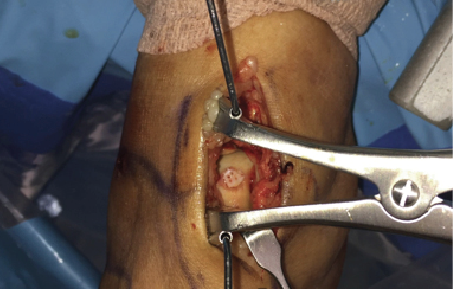

Depicted in the photos above is a case involving the treatment of an osteochondral lesion of the first metatarsal head with BioCartilage. One would appropriately prepare the lesion of the metatarsal head with debridement and drilling. Reconstitute the morselized cartilage allograft with whole blood, platelet rich plasma or concentrated bone marrow aspirate, and apply the allograft. After fully applying the allograft, secure it with a fibrin glue product.